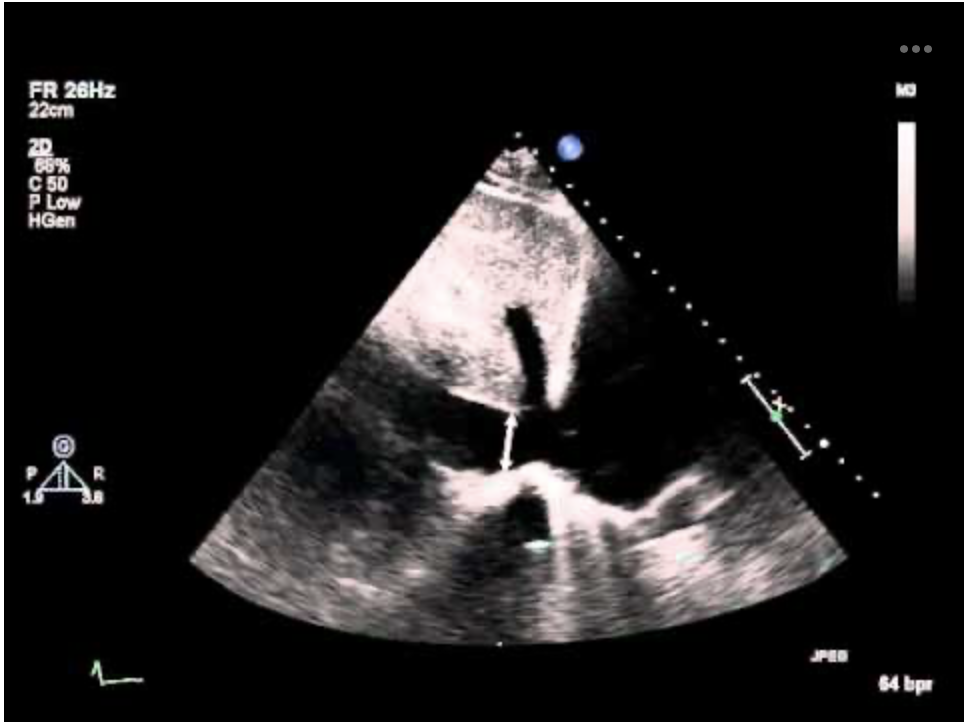

The measurement arrow is in the ______ in this _____.

IVC, Subcostal